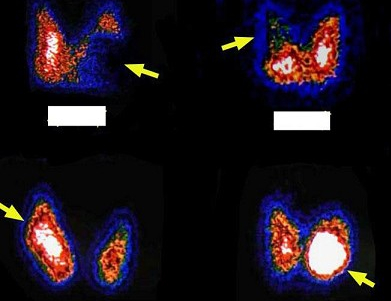

34岁男,左侧髋关节外伤伴脱位半年,左下肢疼痛、跛行半个月,行双侧髋关节断层显像如图,可能的诊断是()

A.左侧股骨头缺血性坏死(早期)

B.左侧髋臼滑膜炎

C.左侧股骨头“甜面圈”征

D.左侧股骨头缺血性坏死(中期)

E.股骨头未见缺血性坏死征象